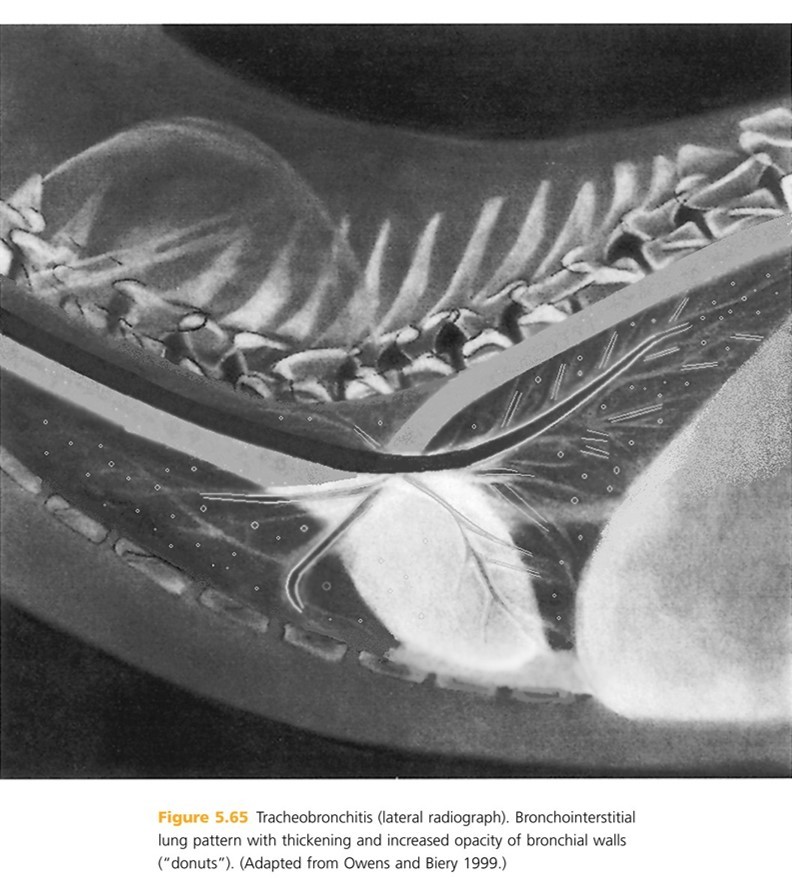

A nonspecific increase in intertitial lung opacity may be present called “____ ____”. Bronchial walls often are ______ and may be increased in opacity. Bronchial walls may appear hazy due to peribronchial ______. Severe or chronic disease can lead to thickening of _____ ____ sometimes with a narrowing of ____ ____ and bronchiectasis

dirty lungs–thickened—Infiltrates— tracheal walls —treacheal lumen